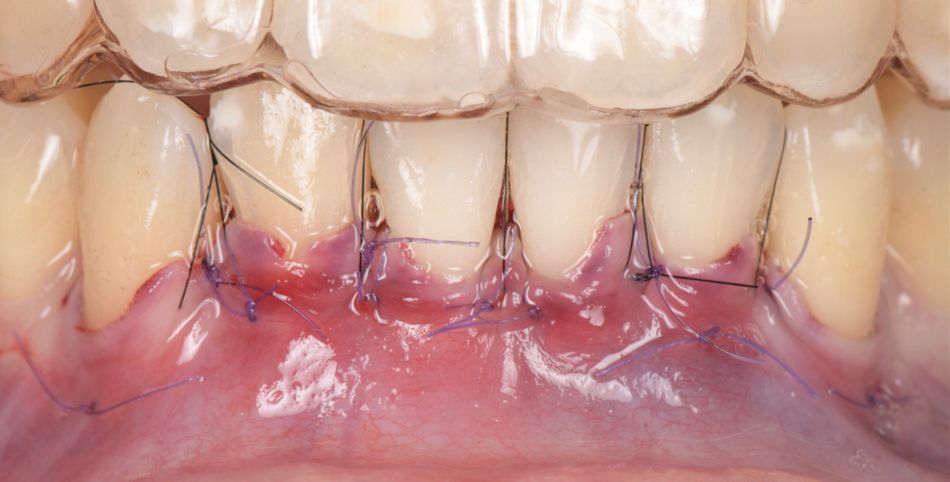

The buccal flaps were coronally displaced and sutured with 6/0 sutures and tension-free closure (Fig. 8).